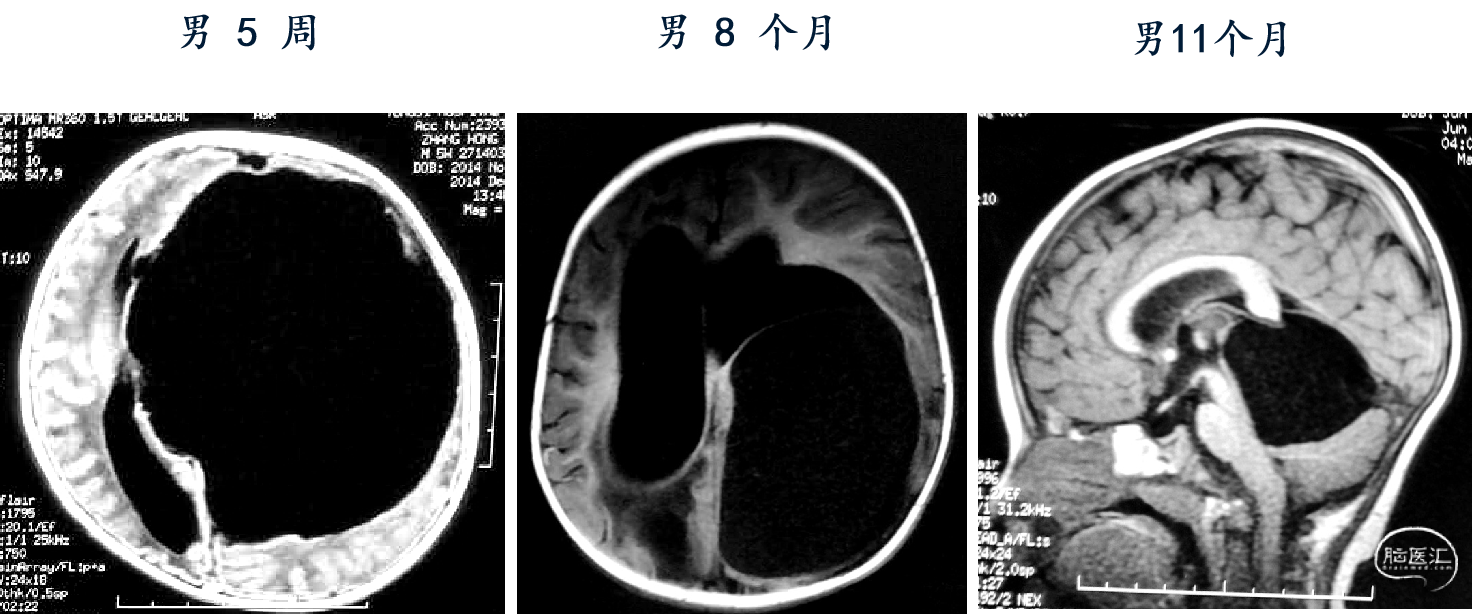

男,5周,囊肿-腹腔分流术

3个月后

22个月后,内镜下造瘘术,泵压力逐步调高

造瘘术后3个月

7岁 小学一年级,成绩较差、余无神经功能障碍

脑组织形态发育接近正常